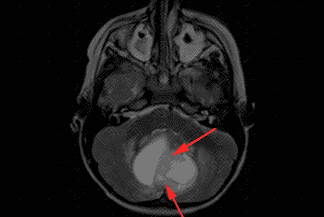

Texto alternativo para a imagem Créditos: Dra. Elazir Mota - Rio de Janeiro/RJ

Descrição da imagem: Na sequência T1 pós-contraste, há intenso realce do componente sólido (seta vermelha).